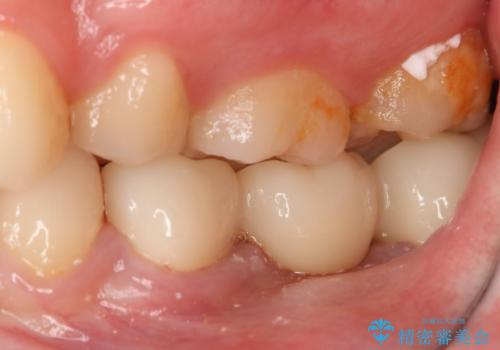

患者様の希望によりフルジルコニアブリッジを選択しました。

- 297000円(フルジルコニアクラウン×3、仮歯×3)費用は治療当時の料金となります

後ろの歯が前に倒れ込んでいましたが問題なく治療を終えることが出来ました。